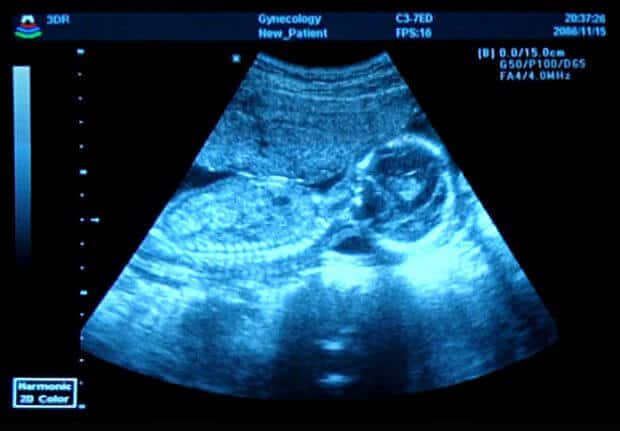

El Ultrasonido Morfologico, también conocido como estructural o de segundo nivel, es sin duda una de las principales pruebas para monitorear el desarrollo de tu bebé. Se realiza entre la semana 20 y 22, esto debido a que es el periodo en el que los órganos pueden verse sin ningún problema. De esta forma, durante el Ultrasonido Morfologico evaluamos el desarrollo de los órganos de tu bebé, por lo que también es posible detectar anomalías en alguno de estos.

El Ultrasonido Morfologico se caracteriza por ser una prueba certera. A pesar de esto, el Ultrasonido estructural puede verse afectado en sus resultados por razones en su mayoría externas. Factores como la posición de tu bebé durante la prueba, si sufres de obesidad o inclusive los gases intestinales pueden impedirnos obtener los resultados que queremos. Pese a esto, la gran mayoría de los resultados son exitosos, ya que los factores que impiden obtenerlos no son muy comúnes, por lo que no debes preocuparte.